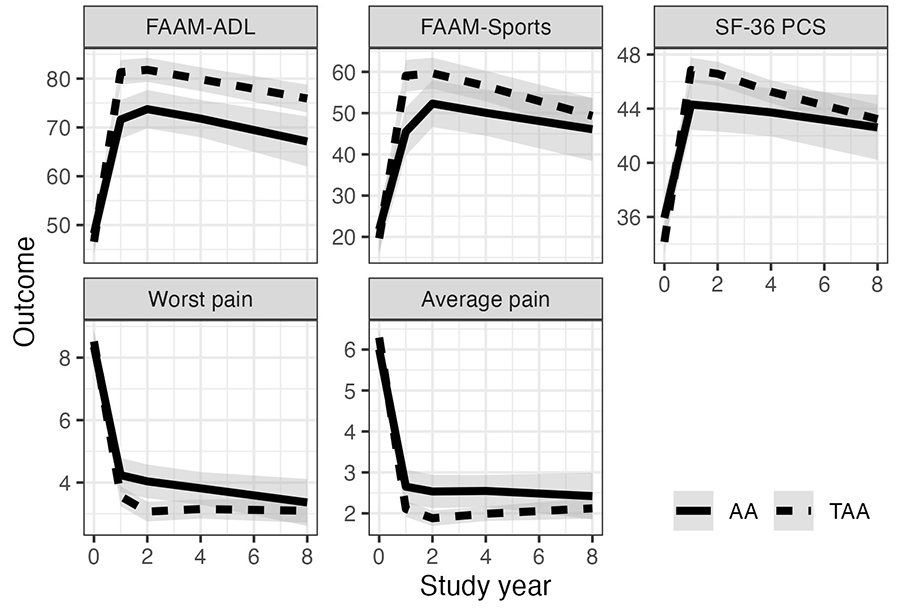

Study: Arthrodesis and arthroplasty show similar benefits for end-stage ankle arthritis

A study presented at the AAOS 2025 Annual Meeting reported that ankle arthrodesis (AA) and total ankle arthroplasty (TAA) are both effective for end-stage ankle arthritis (ESAA) up to 8 years.

-